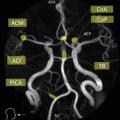

Le scanner doit être réalisé en urgence. Il montre une hyperdensité des espaces sous-arachnoïdiens, évalue la sévérité par l’échelle de Fisher et recherche les complications précoces (fig. 1 et tableau 1).